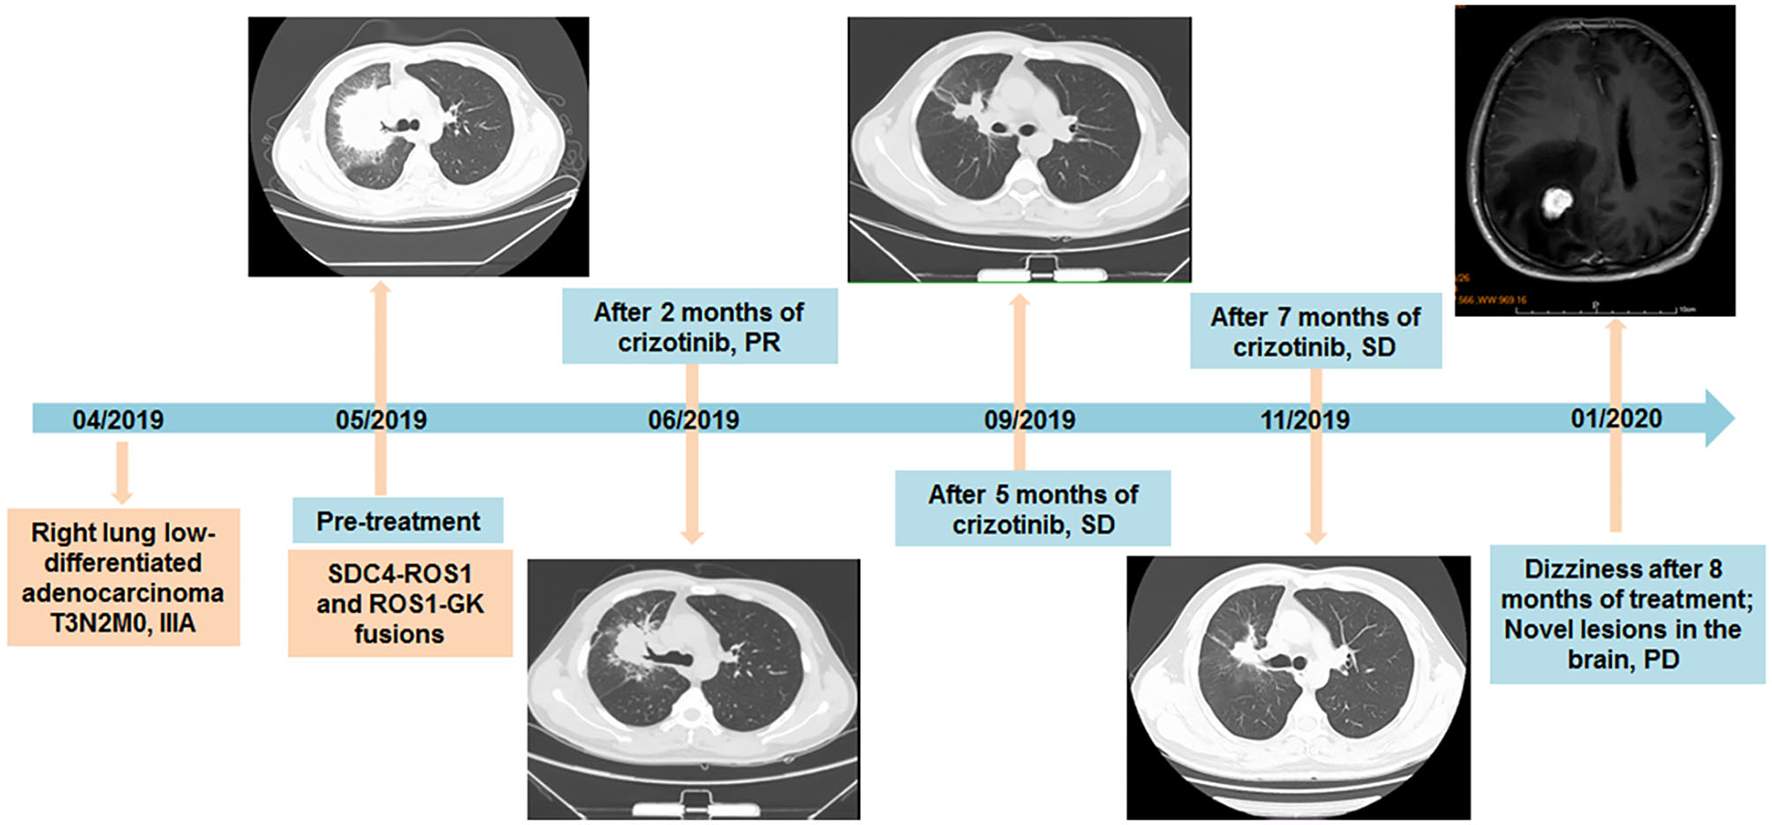

Figure 2

Timeline of diagnosis and treatment of the patient, with CT and MRI scans of lesions during the treatment of crizotinib additionally provided.

Considering the existence of crizotinib-sensitive SDC4-ROS1 fusion, the patient was treated with crizotinib 250 mg orally twice daily as first-line treatment since May 2019. After 2 months of treatment, the cough significantly improved, and a follow-up CT suggested a partial response in the lung lesions (4.2 cm × 3.3 cm) according to the Response Evaluation Criteria In Solid Tumors v1.1. The follow-up CT examinations at 5 and 7 months after treatment showed that the lung lesion was stable compared with previous examinations (Figure 2). In February 2020, the patient was admitted to the hospital for 1 month of progressively aggravated headache, dizziness, vomiting, and nausea. The MRI revealed an iso-signal shadow with a diameter of 0.8 cm and 2.1 cm in the right frontal lobe and parietal lobe, respectively, suggesting metastatic lesions in the brain (Figure 2). Then, the patient was treated with gamma knife to brain lesions in March 2020. After radiotherapy, the headache of the patient was basically relieved, with occasional dizziness and no severe nausea and vomiting. Therefore, no further systemic treatment was given. In May 2020, the patient reported slight fatigue and no new symptoms and other obvious discomfort. Chest CT was performed, and no significant change was found in the lung lesions. Moreover, no significant abnormalities were found during the brain MRI reexamination. In May 2020, the patient began the treatment of traditional Chinese medicine by himself. During the follow-up inquiry in July 2020, the patient complained of anorexia, occasional nausea, and no other discomfort symptoms.